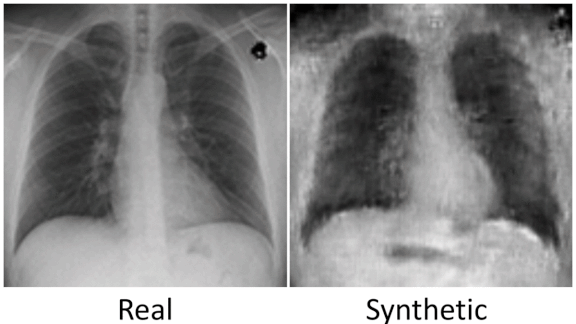

Contrast between real and real and synthetic datasets

Battling Bias in Synthetic Data: How synthetic data startups are working to avoid bias

Synthetic datasets can inherit flaws in the real-world data they’re based on. Startups are working on solutions. Generating synthetic datasets for training machine learning systems is a booming business.